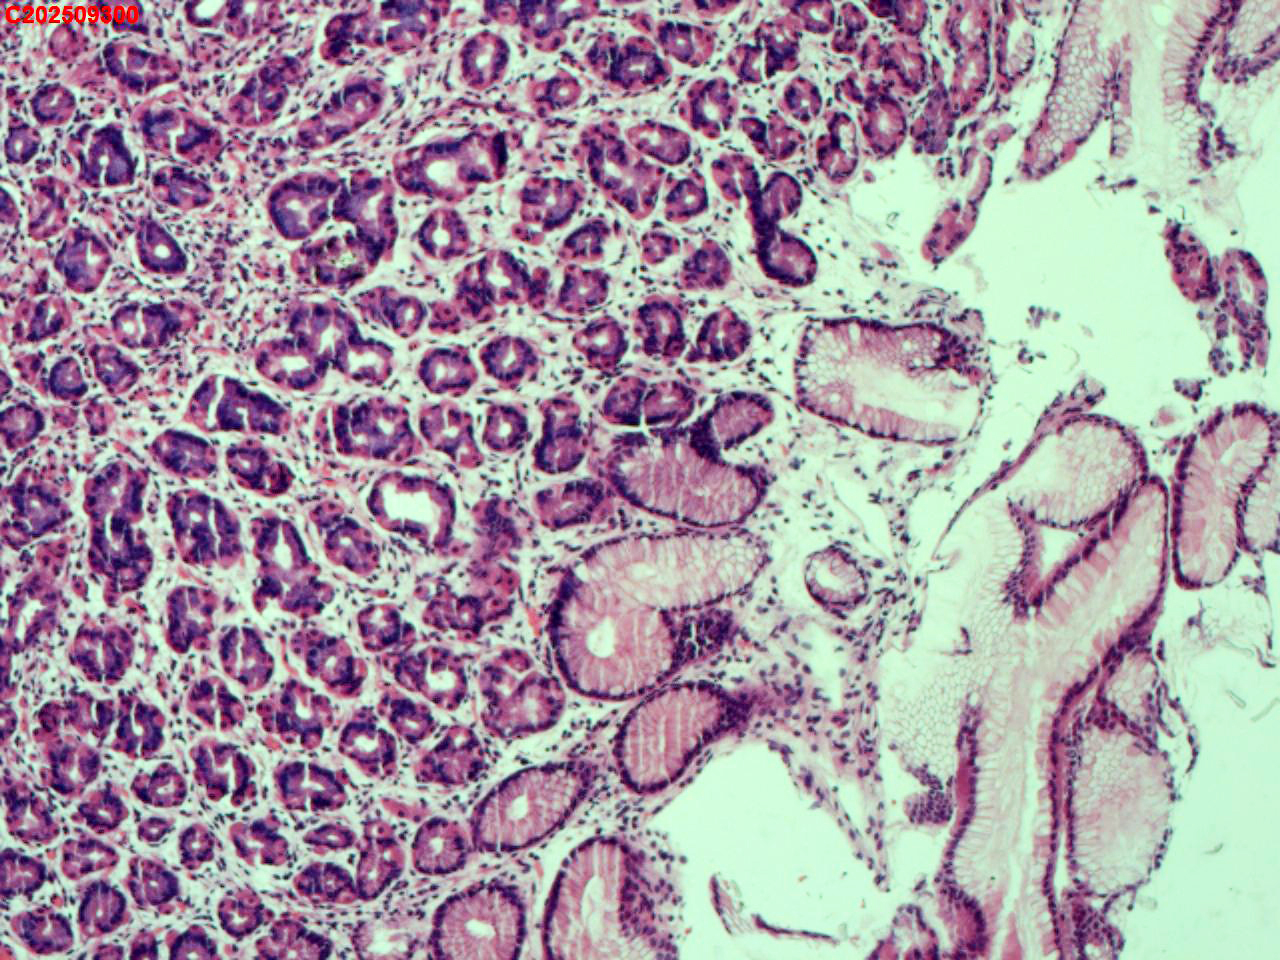

胃底粘膜

性别

女

年龄

44岁

临床诊断

胃息肉

一般病史

体检

标本名称

大体所见

胃底:可见一枚直径约2mm的半球形息肉。

增生性息肉